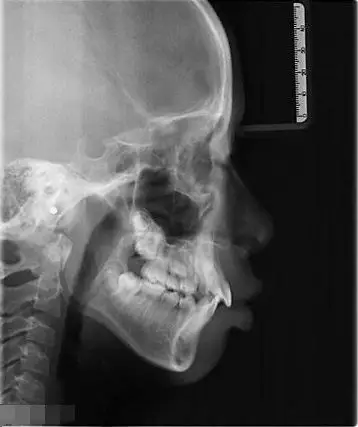

友们会看牙片吗求帮我看看这是骨性还是牙性地包天

准备研究资料及诊断记录:模型,x光片(曲断,头颅侧位,关节片),面颌像等

你还看不懂x光片?徐医生带你全面解析

牙科治疗的颌面x光片.口腔正畸诊断

需要正颌吗?(内附侧面照及x光)

牙齿矫正科普丨初诊拍片都做不好,也敢叫正规牙科?